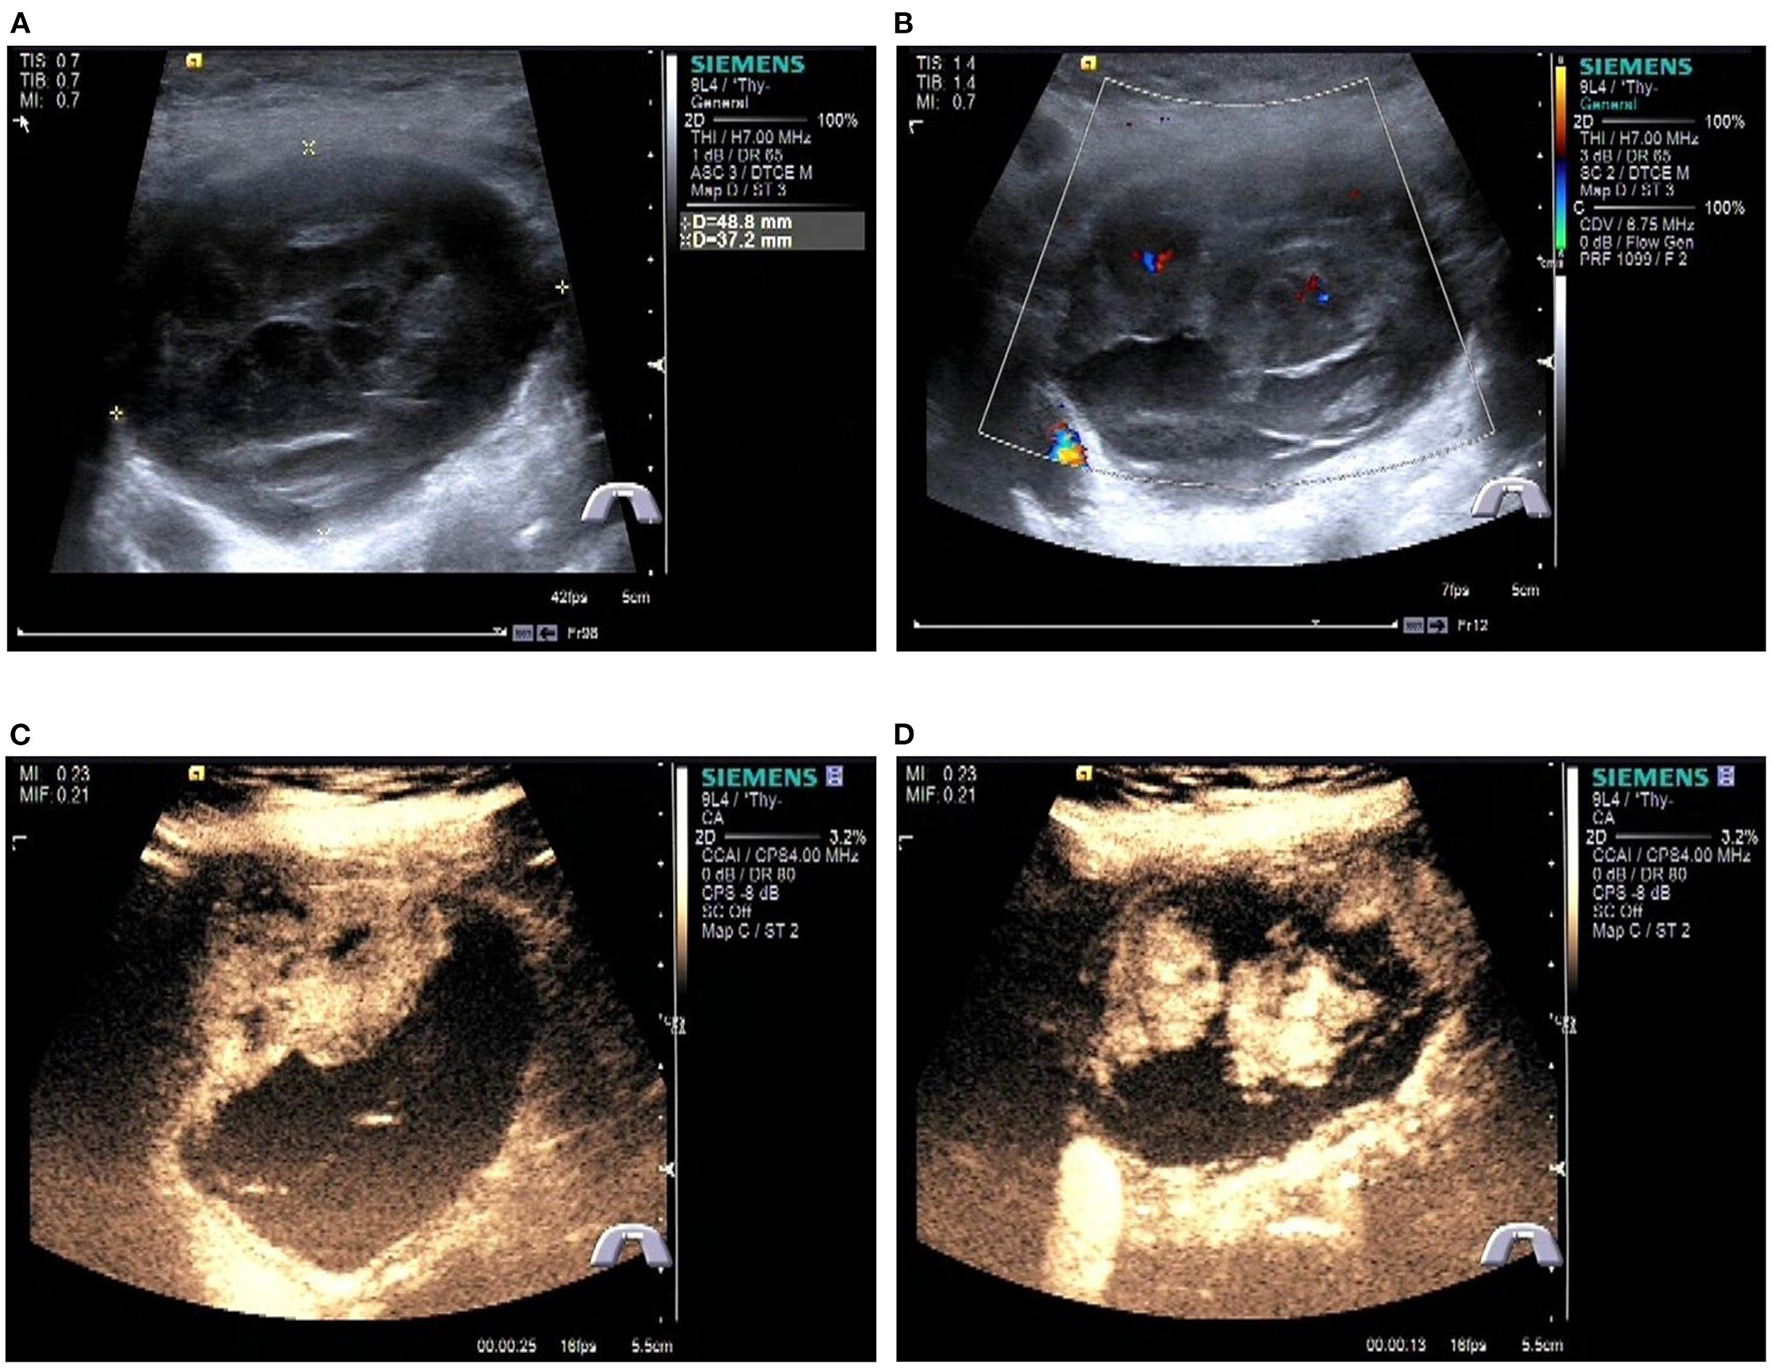

Figure 2

Preoperative contrast-enhanced ultrasonography of the patient. (A) Gray scale ultrasonography of the mass. (B) Color Doppler imaging of the mass. (C, D) Contrast-enhanced ultrasonography of the tumor.

A Blood test showed no obvious abnormalities. The level of thyroid hormone and calcitonin is in the normal range. No abnormalities were found in the laryngoscopy, chest X-ray, and chest CT. Contrast-enhanced ultrasonography showed a heterogeneous echoic, cystic-solid mixed mass ~48.8 × 37.2 mm in the isthmus of the thyroid gland. The mass is with clear boundary, regular shape. In total, 0.6 ml perflubutane microspheres were injected through the elbow intravenous for CEUS. The isthmus nodule was mostly equally enhanced and partially no enhancement. The peripheral nodule showed annular enhancement. No obvious enlarged lymph nodes were observed in the cervical region. The mass was classified as TI-RADS 3 (Figure 2). CT scan showed a mass lesion in or below the isthmus of the thyroid gland. The mass was heterogeneous density. There are microcalcifications and liquefaction necrosis areas inside the mass. The average CT value is 28 HU. The edge of the mass is mostly clear. The contrast-enhanced CT demonstrated heterogeneous enhancement. The degree of enhancement is lower than that of the normal thyroid gland. The average CT value is 58 HU. There are multiple small lymph nodes in the I-II area of the cervical region. The CT could not establish a confirmed diagnosis but a low-grade tumor could not be ruled out (Figure 3).